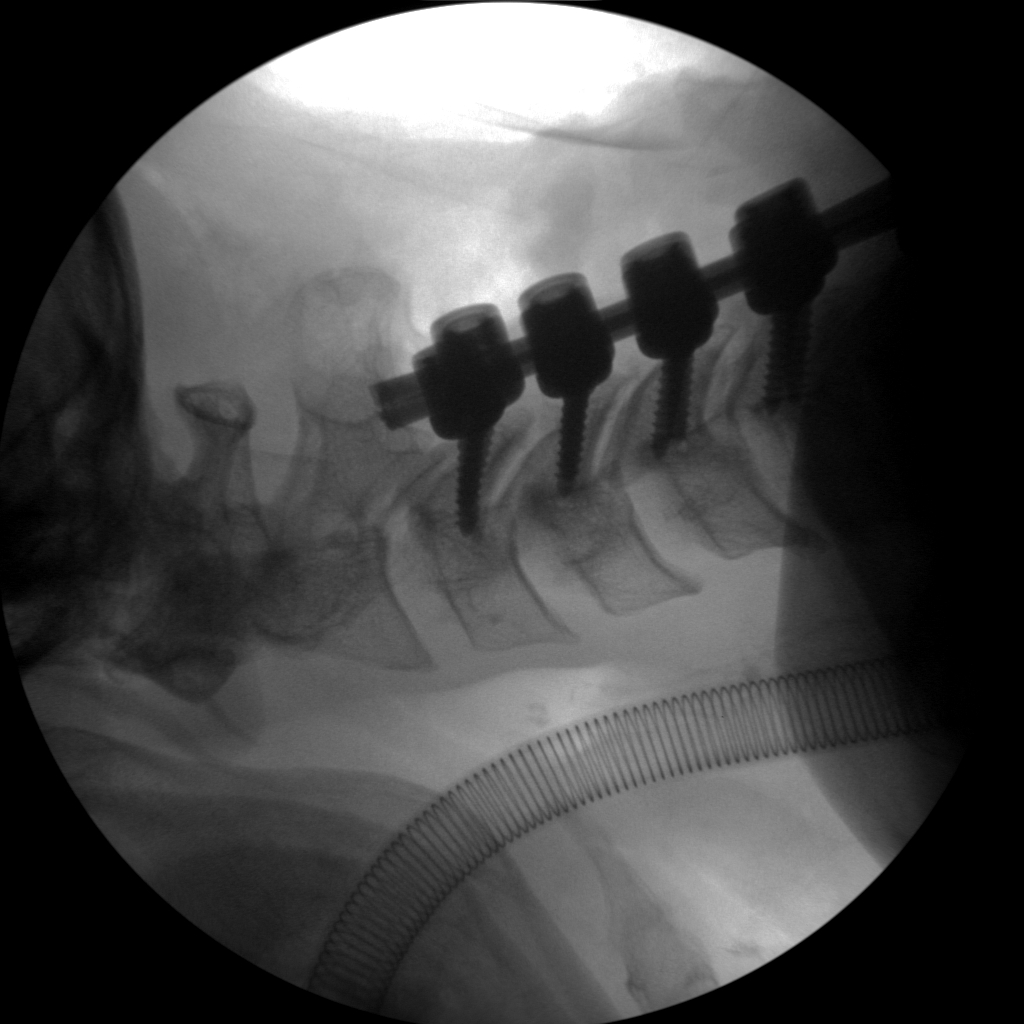

High-quality imaging

Skan-C uses advanced imaging technology, such as pulsed fluoroscopy and digital subtraction angiography, to provide highly detailed images of the affected area. This allows doctors to perform procedures with increased precision and accuracy, and better patient outcome

Clinical Evidence

Skan-C is a great C-arm for neurology treatments for several reasons